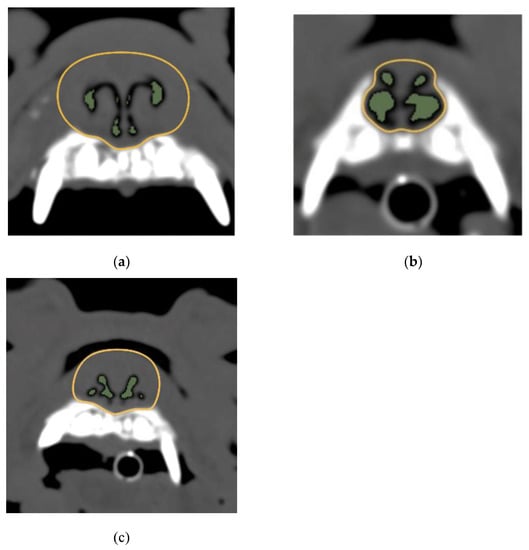

2.3.1. 2D Region Growing

2.3.2. Measurement of the AA/NC Ratio